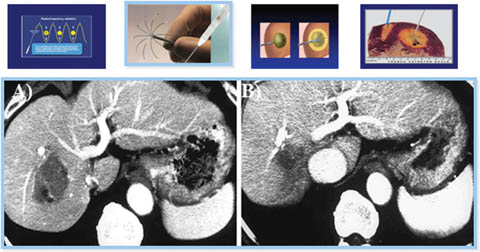

Percutaneous ethanol injection

Percutaneous ethanol injection (PEI) involves the imaging guided injection of ethanol into the tumor to induce coagulation necrosis (Figure 8) (66, 72). The non-subcapsular, non-perivascular nodules <2 cm are ideal for PEI because of its limited capacity to penetrate the tumor beyond its pseudo-capsule or fibrotic septa (60, 72). Although it is a cost-effective form of therapy, the recurrence tumor rate is higher when compared to other locoregional therapies, thus PEI has fallen into disfavor as the first line therapy for small HCC lesions. PEI has a recurrence-free survival rate of 77% at one year as compared to 86% in patients treated with radiofrequency ablation (RFA) (64). Its side effects include post procedural pain, and it requires several sessions to yield complete treatment (66).

Fig 8

Figure 8. Ultrasound-guided percutaneous alcohol injection of hepatocellular carcinoma. A and B. Under image-guidance by US, administration of ethanol (97%) is performed into the tumor. C. Noting an enlarging hyperechoic signal. Although the procedure in well-trained hands is reliable and practical for large scale application, malignant recurrence rates are high.

Radiofrequency ablation

Image-guided RFA is indicated in patients with tumor lesions ≤3 cm (single or up to 3 lesions) or single lesions ≤4 cm, not in proximity to major vascular or biliary conduits, with intact liver function belonging to Child-Pugh A or B group and ECOG status 1-2 (72, 73). The heat emanated from high frequency oscillating electrical currents at the needle tip of the probe transforms dripping NS0.9% into vapor, resulting in tissue necrosis (Figure 9) (66, 72, 74). However, the thermal effect is dissipated by the “sink effect” of a vessel in proximity and by the size of the tumor (72).

Fig 9

Figure 9. Image-guided radiofrequency ablation for hepatocellular carcinoma. Under ultrasound-guidance, a radiofrequency ablation needle is placed near the center of the tumor. A. Alternate current at high frequency turns the needle tip temperature into a thermal injury with a subsequent death zone. B. At 3 months follow-up, the death zone has contracted.